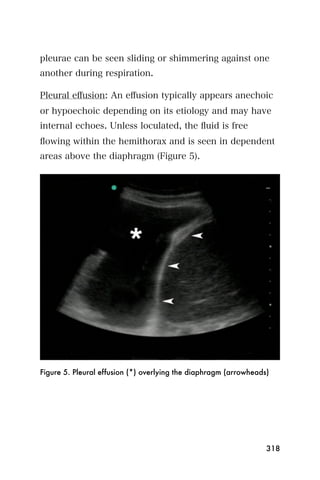

254

• Be careful not to confuse the inferior vena cava or

other fluid filled structure (like a pancreatic cyst) with

the aorta.